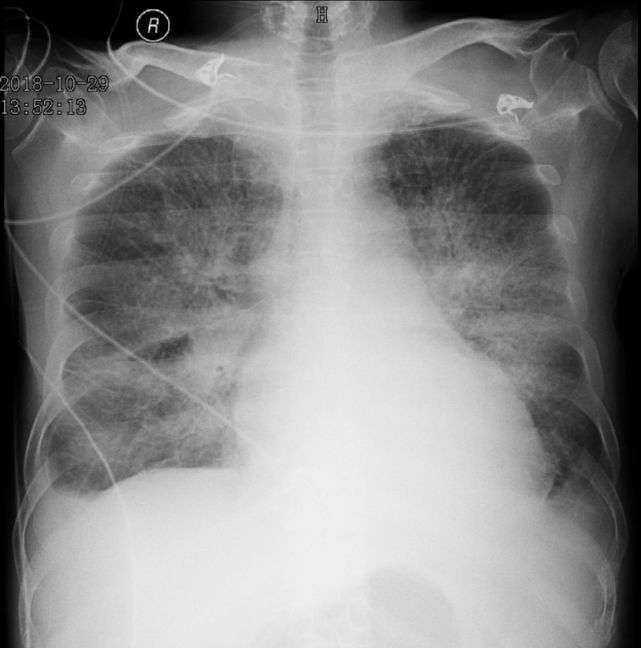

(3)X 线检查哮喘患者常无明显异常,而心衰患者可见心影增大,肺淤血症表现,典型者呈蝴蝶影(图 3)。

图片

图 3 全胸片示心影增大,典型「蝴蝶影」,双侧肋膈角钝模糊,提示心衰、急性肺水肿。